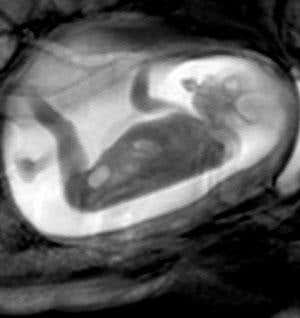

In a fluid bubble within softly padded walls, the little fetus scratches her chest. Taking a run-up, she repeatedly launches herself at the uterine wall, a juvenile Jackie Chan practising her gravity-defying moves.

Looking at the video later, it looks like my womb boxer is really giving it some. Encased in the narrow beige tunnel of a magnetic resonance imaging (MRI) machine, however, I felt only a single soft thud, like a kernel of corn popping in my belly.

This is the cutting edge of fetal imaging. Researchers from Imperial College London are using MRI to take multiple high-resolution snapshots of fetuses and their brains and then stitch them together using software into cinematic sequences, providing a unique insight into life inside the uterus (see video, above).

However, such imaging is also providing a unique opportunity for studying complex fetal movements in situ. “With ultrasound you have a relatively limited view, and beyond 32 weeks you can only really see parts of the body moving,” says Imperial’s Mary Rutherford, who is leading the research.

MRI enables sharp images of the entire body to be recorded – critical if fetal movements from different stages of development are to be compared with one another, which is what Rutherford’s team is trying to achieve. “We’re interested in how the fetus moves, how this changes during gestation and whether there’s a difference between normal fetuses and those that aren’t developing properly,” she says.